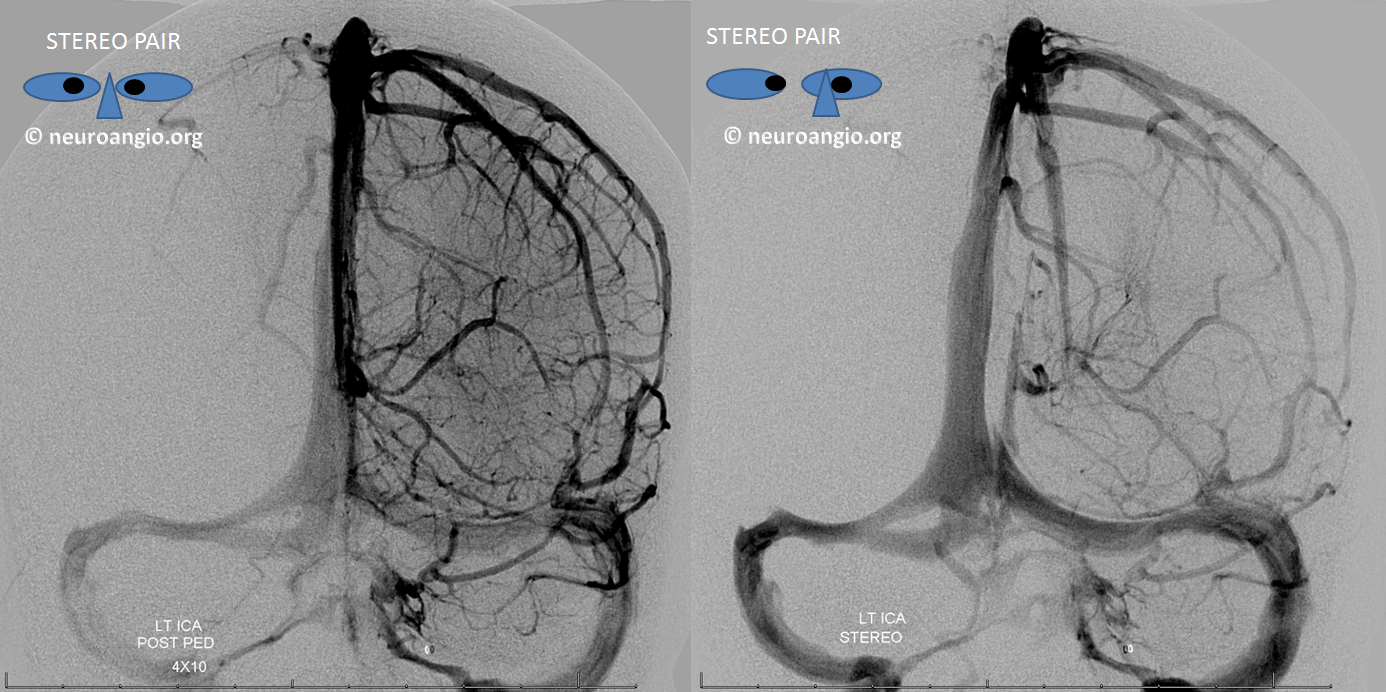

All of the above anatomic knowledge can become very useful in evaluation of venous thrombosis. Numerous collateral pathways develop in this setting attempting to compensate for the loss. The most dramatic cases usually involve the largest channel — the superior sagittal sinus. In this case, a man presented with what initially was thought to be vasculitis-related brain hemorrhage. Subsequent workup led to an angiogram, where sagittal sinus thrombosis with extensive trans-cerebral and trans-osseous emissary vein collateral channels was seen. In retrospect, these findings were present on the patient’s earlier contrast MRI. “Venovibe” or other contrast-enhanced MR venograms can very sensitive, particularly when interpreted with the appropriate index of suspicion. Noncontrast 2-D time of flight MRV I consider to be next to useless as a problem-solving technique. Any thin-slice postcontrast T1 study is vastly superior.